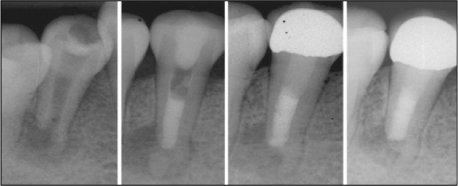

Figure 2

Root canal treatment and follow up.

MTA, mineral trioxide aggregate.

Figure 2 Root canal treatment and follow up. MTA, mineral trioxide aggregate.